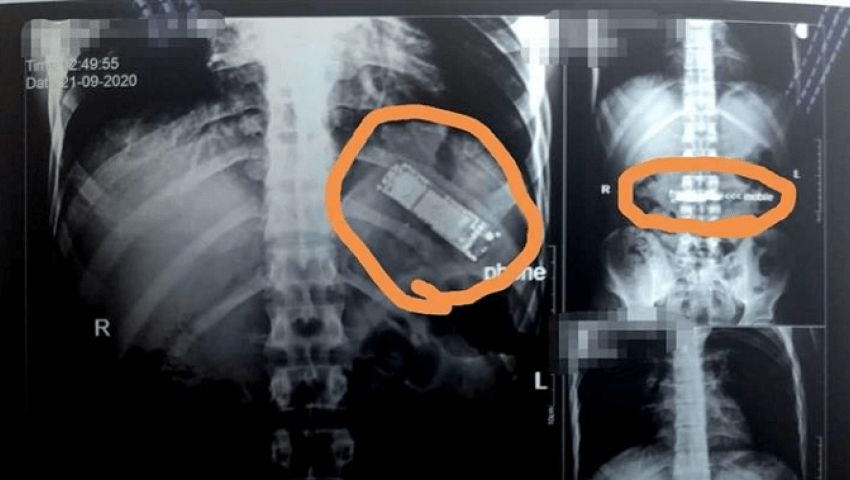

واستقبل المستشفى مريضا يعاني من ألم شديد في البطن فأجريت له أشعة وفحوصات طبية كشفت عن وجود التهابات شديدة في البطن والأمعاء، فقرر الأطباء فتح غرفة العمليات فورا لإنقاذ حياة المريض.

وعلى الفور، قام طاقم الجراحة بمستشفى أسوان الجامعي بإجراء عملية، وقاموا باستخراج جسم غريب من معدته، تبين أنه هاتف جوال صغير حيث قام الفريق الطبي باستخراج الهاتف من معدة المريض، وهذه تعد الواقعة الأولى من نوعها.